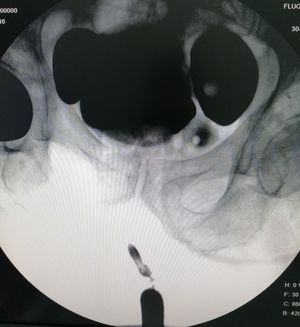

Retrograde urethrocystography

Urinary bladder diverticuli in patient with severe urethral stricture